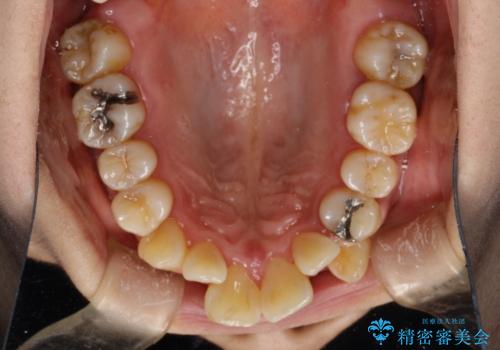

- これから矯正治療を始めるため、今の状態でも歯をきれいにしておきたいとのことでした。PMTC60分コースを行いました。

プラーク(細菌の塊)や歯石がたまると歯の表面はザラつきいてきます。そのザラつきは歯周病や虫歯菌の棲家となります。そのまま放置すると、歯肉が腫れてきたり、歯肉から出血したり、口臭が強くでたりします。とくに歯肉の境目は、歯磨きで汚れを除去することが難しく、プラーク(細菌の塊)や歯石が溜まりやすい場所です。

歯並が、がたついている場合はなおさら汚れが溜まりやすいです。矯正治療前や矯正中、定期的にPMTCをすることで、矯正治療中の歯肉トラブルを防ぐことにつながります。